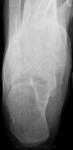

Здравствуйте! Я - молодой доктор, оставшийся один в отделении на целый месяц. Непонятных мне снимков много, вот отдин из них. Женщина 1938г.р., направлена на снимки голеностопного сустава с диагнозом: Артроз. Артроза не вижу, но пяточная кость вызывает подозрения. Что это может быть? Помогите разобраться.

Киста пяточной кости.

На самом деле, я бы в заключение вынесла "кисту" и рекомендовала МРТ

К вопросу о пяточной кисте...Является ли участок разрежения костной структуры на верхней поверхности пяточной кости кистой?

а мне кажется там киста